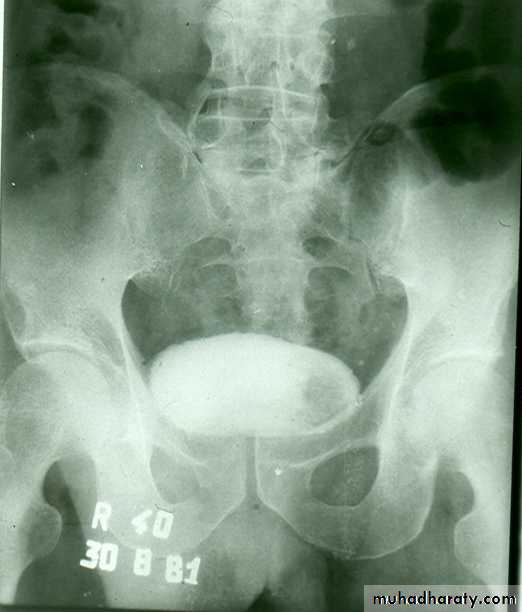

• IVU ( cystogram stage )

• * Elevated bladder base .• *Lower ureter elevated and curved (fish hook ).

• * Back pressure to both kidney & ureters .

• * Thick trabeculated bladder wall and diverticula formation .

• * Large size prostate produce filling defect like appearance .

• * Post-voiding residual volume .